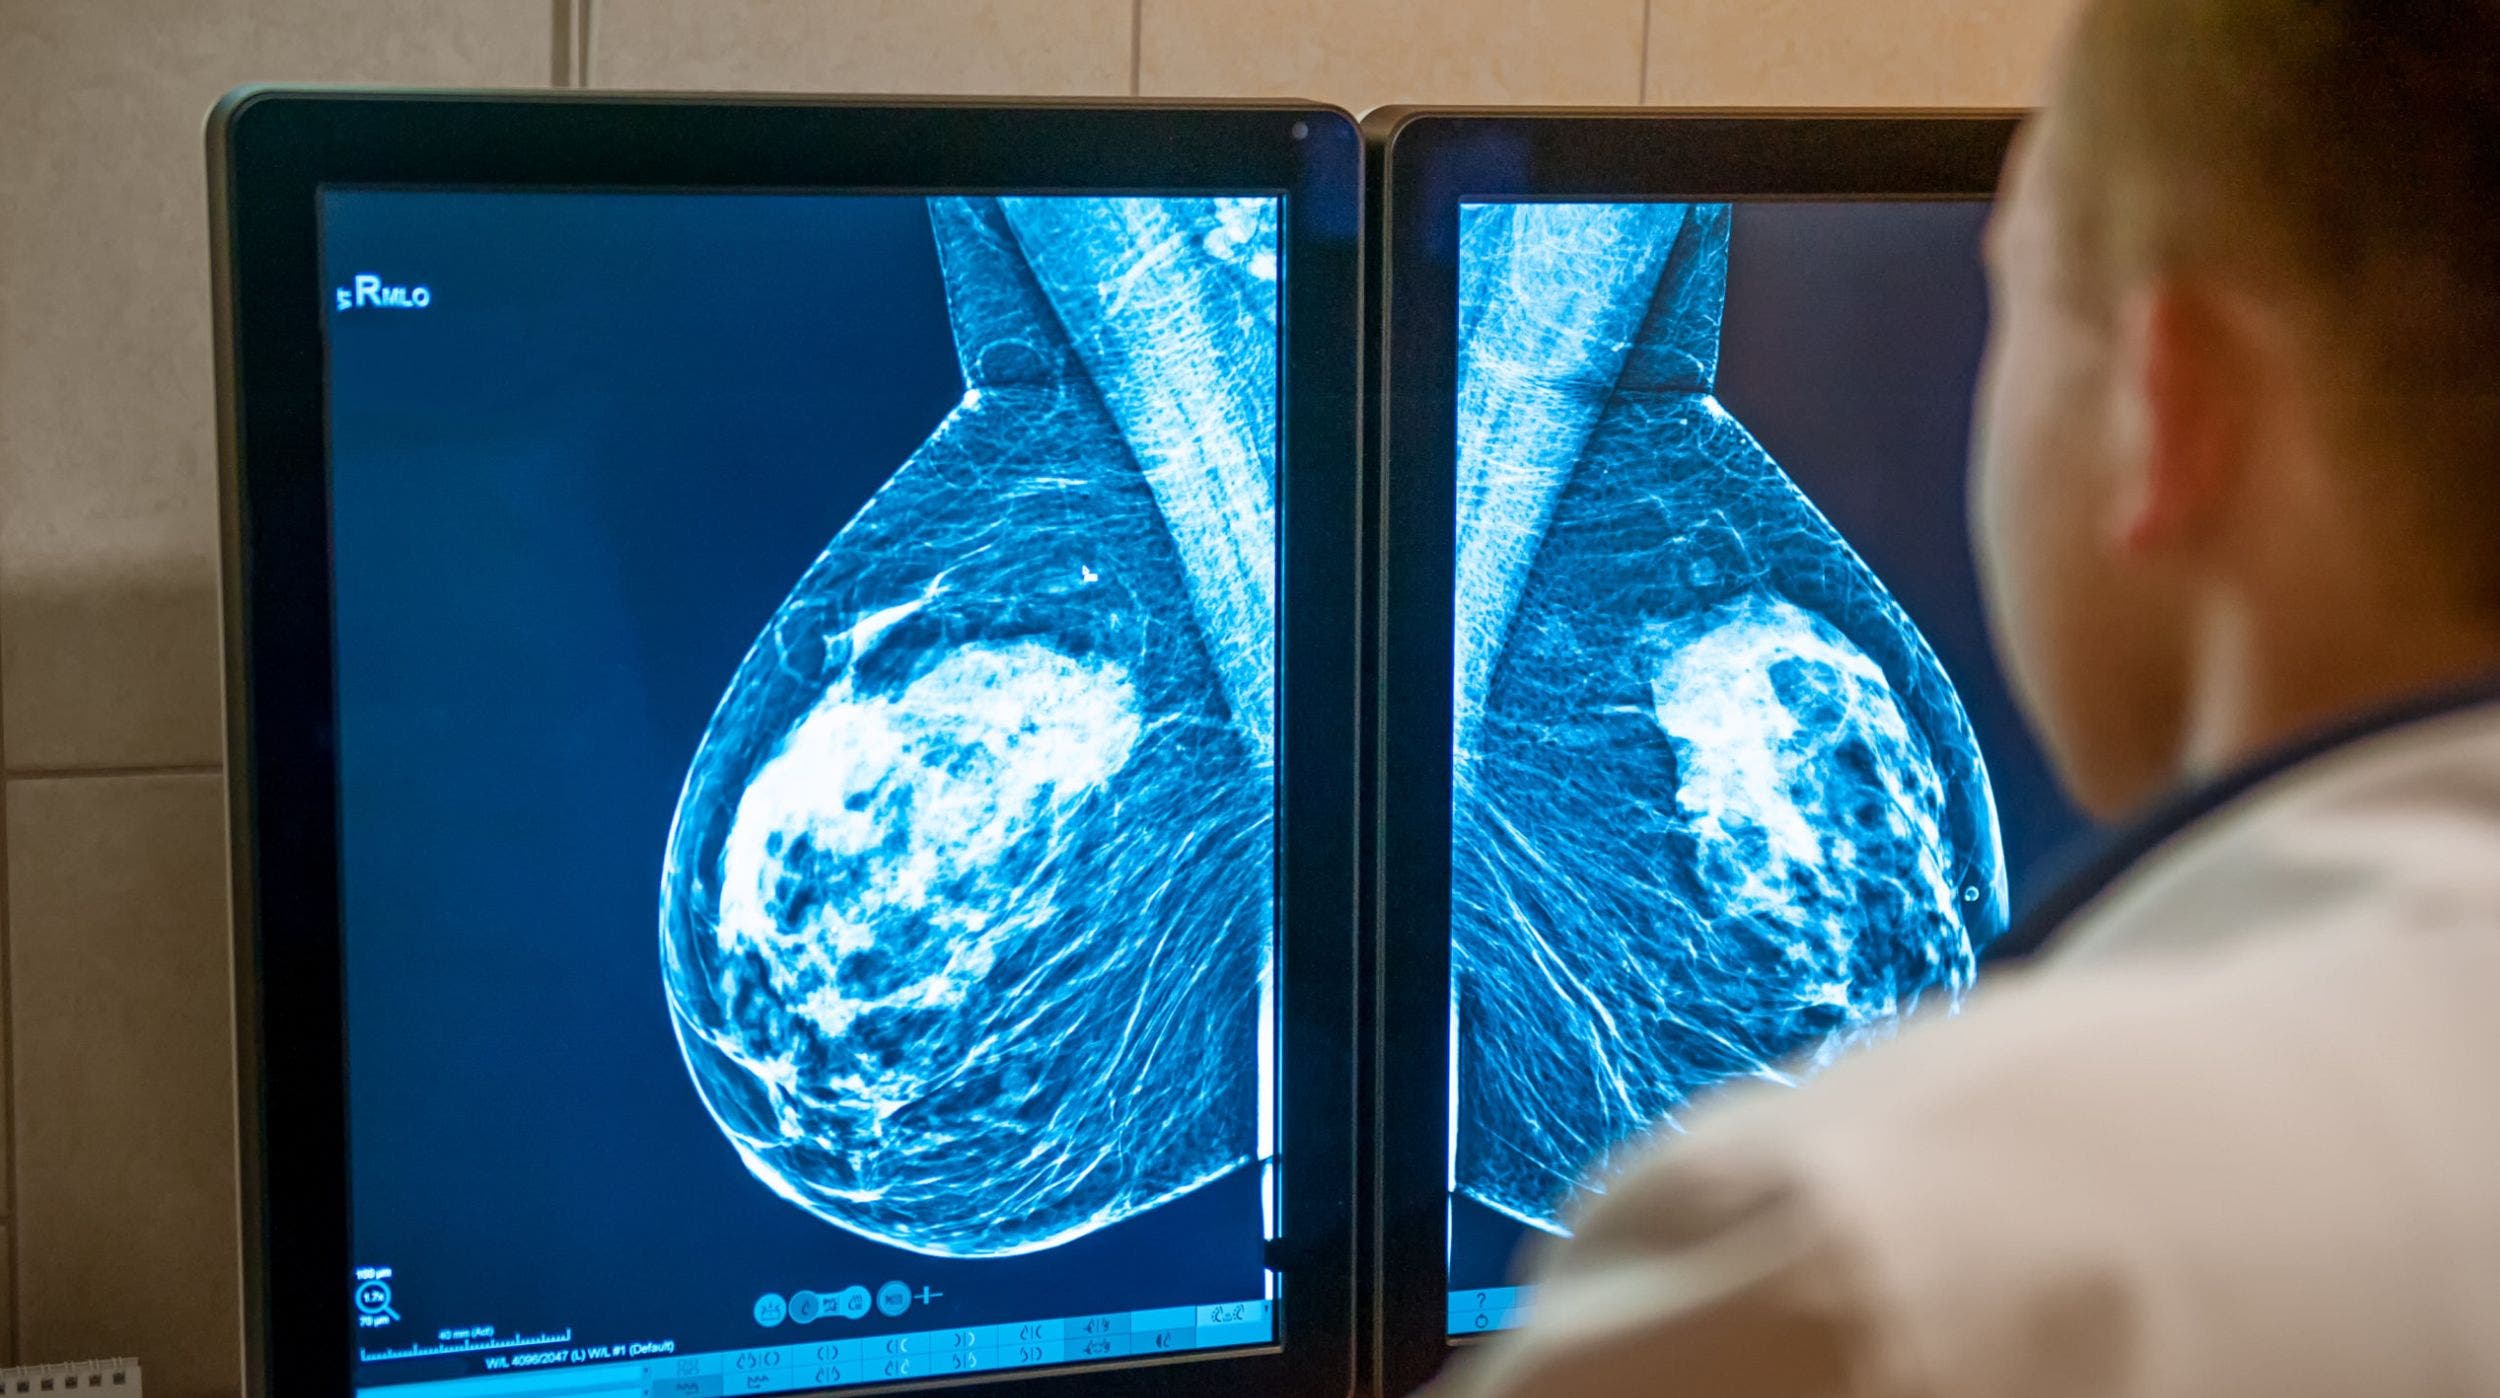

Incluso cuando se detectan a tiempo, algunos tipos de cáncer son más agresivos y mortales que otros. Este es el caso, por ejemplo, del cáncer de mama triple negativo que representa del 10 al 15% de todos los cánceres de mama. Este cáncer afecta a 225 mil pacientes en todo el mundo.

Alrededor de la mitad de los pacientes desarrollarán recidivas (reaparición de una enfermedad) locales y metástasis, independientemente del tratamiento que reciban. Actualmente, ningún tratamiento específico es capaz de prevenir estos dos eventos. Los pacientes que padecen cáncer de mama triple negativo generalizado tienen sólo una posibilidad entre diez de curarse.